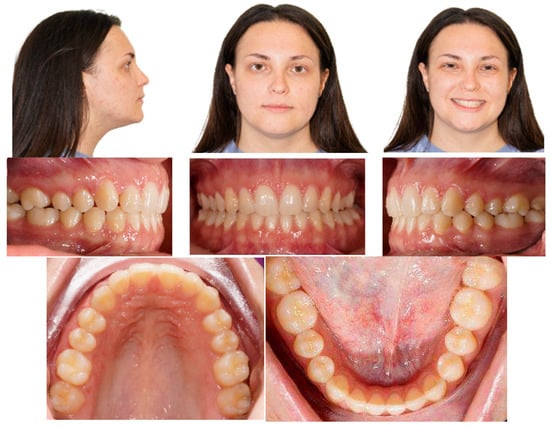

Post-treatment records of the patient successfully treated using a combination of cantilever mechanics with TADs and clear aligners show a control of the facial aesthetics from the frontal and lateral perspectives with a harmonious soft-tissue profile. Final clinical records show good aesthetics and the functional recovery of the upper canines in the arch. A Class I canine relationship was achieved, and overbite and overjet were normalized. The correction of crowding was carried out (Figure 17).

Figure 17.

Post-treatment extraoral and intraoral pictures.

At the end of the treatment, cephalometric radiographs show the good control of the upper and lower inclination. The radiographic evaluation shows an ideal root parallelism and a preserved periodontal health in the canine region (Figure 18). Retention was achieved through Vivera in the upper arch and via a bonded lingual retainer in the lower arch. No TAD failures were observed.

Figure 18.

Final radiographs and landmarks.